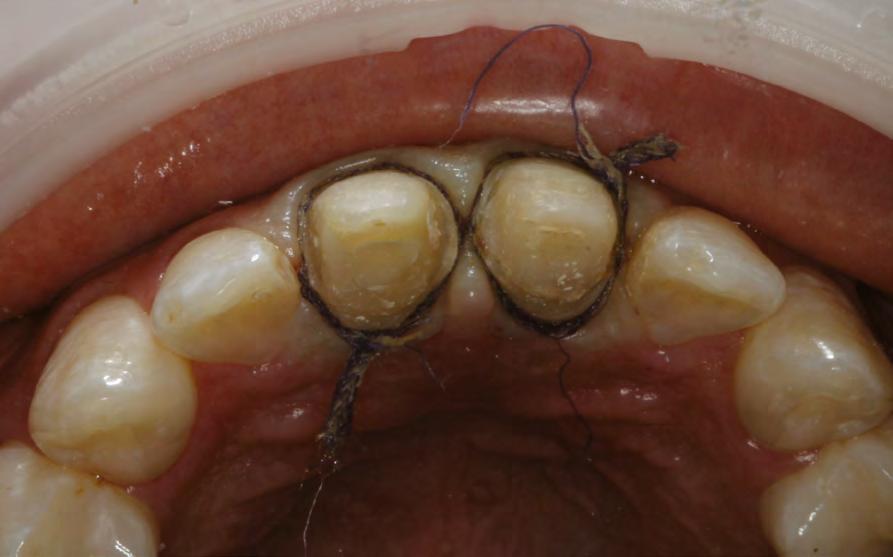

en paciente adulto tratado con extracciones de primeros molares permanentes. Reporte de caso

Dentista y Paciente 52 Sonriendo al futuro

Extraer los primeros molares permanentes puede ser una opción de tratamiento en ciertos casos de ortodoncia, como aquellos con apiñamiento moderado, biprotrusión, mordidas abiertas, o problemas de clase II y III que requieran extracciones. Además, se considera esta opción cuando los primeros molares están afectados por caries extensas u otras afecciones, lo que los hace más adecuados para la extracción y evita tratamientos restaurativos extensos o la necesidad de implantes en el futuro. Este artículo presenta el caso de una paciente en el que se optó por extraer los primeros molares superiores e inferiores para lograr resultados clínicos óptimos tanto en términos faciales como oclusales.

Palabras clave: extracción, primer molar, maloclusion, tratamiento ortodoncia.

Las extracciones dentales en los tratamientos de ortodoncia pueden ser indicadas en casos de caries extensas, restauraciones deficientes y/o extensas en premolares sanos, patologías periapicales, apiñamiento posterior y mordidas abiertas anteriores. La extracción de primeros molares permanentes es uno de los muchos planes de tratamiento en algunos casos de ortodoncia, en los cuales se presentan situaciones donde los primeros molares se encuentran comprometidos por lesiones cariosas extensas o alteraciones del desarrollo, por lo cual pueden ser candidatos para ser extraídos en casos donde se realizará tratamiento ortodóntico de pacientes como en los que se presentan apiñamiento moderado, biprotrusión, mordidas abiertas, clase II y III, casos en los cuales es necesario realizar exodoncias. Las extracciones posteriores producen una rotación antihoraria mandibular lo que podría ser conveniente en pacientes cuyas características faciales no se deben comprometer, como en pacientes con ángulo nasolabial obtuso, donde una significativa retracción de los dientes anteriores podría causar mayor apertura de este, lo que representaría en un resultado estético negativo y en camuflaje de pacientes clase II esqueléticas (extracciones superiores) y III (extracciones inferiores).1

189. Mayo 2024 53 Tratamiento ortodóncico

Cerrillo Lara Daniel. Ibarra Ramiro Jaime Tadeo. José de Jesús Anaya. Universidad Autónoma de Baja California. Campus Tijuana. Especialidad en Ortodoncia

Reporte del caso

Paciente del sexo femenino de 39 años de edad, sin datos patológicos aparentes, acude a la clínica de ortodoncia de la Facultad de Odontología campus Tijuana en diciembre del 2016. Su motivo de consulta fue: "Tengo el diente de abajo mal acomodado" En las fotografías extraorales se observa un paciente mesomorfo, biotipo mesoprosopo, línea superciliar asimétrica, línea bipupilar simétrica, nariz asimétrica, línea comisural asimétrica, labios medianos, tercio inferior aumentado respecto al medio y superior. Presenta perfil convexo, con un ángulo nasolabial obtuso (100°), surco mentolabial (122°). Línea dental superior desviada hacia la izquierda con respecto a línea media facial, muestra 100% de coronas dentales al sonreír. En el análisis intraoral se observa dentición permanente, líneas medias no coincidentes, microfracturas de OD #11 Y #21, clase molar indeterminada bilateralmente por ausencia de OD #16 Y #26, clase I canina bilateral, forma de arcada ovoide en superior, apiñamiento leve, #11, #12, #21 mesiorotados y #25 distorotado, forma de arcada ovoide en inferior, apiñamiento leve y OD #41 lingualizado, presencia de torus mandibular. Sobremordida horizontal de 2 mm y vertical de 20%. En el análisis radiográfico se muestran 26 dientes presentes en boca, ausencia de OD #16 y #26, presencia de #18, #28, #38 y #48 retenidos, altura de ramas mandibulares simétricas, densidad ósea

uniforme, relación corona-raíz 1:1; se observa además una maloclusión clase II esquelética, con crecimiento vertical, dientes anteroinferiores proinclinados así como los anterosuperiores.

Objetivos del tratamiento

Mejorar perfil del paciente, lograr clase molar I bilateralmente con mesialización de #37 y #47, después de extraer primeros molares mandibulares, mantener clase I canina bilateralmente, así como las sobremordidas vertical y horizontal, eliminar apiñamiento, corregir líneas medias, obtener oclusión funcional.

Plan de tratamiento interdisciplinario

Se remite al área de cirugía de la facultad de Odontología para extracciones de los OD #36 y #46 con el fin de armonizar la arcada inferior con la arcada superior, para después proceder a la mesialización de OD #37 y #47.

Plan de tratamiento ortodóncico

Se colocó aparatología fija superior e inferior tipo Alexander slot 0.022, se prosiguió a la alineación y nivelación, expansión superior e inferior con secuencias de arcos, mesialización de OD #37 y #47, recontorneo interproximal inferior, torque de raíces, armonización de arcadas, extracción de terceros molares inferiores y valoración de los superiores, retención removible superior e inferior.

Dentista y Paciente 54 Sonriendo al futuro

Figura 1. Fotografías extraorales de frente y de perfil. Figura 2. Fotografías intraorales iniciales.

Resultados

Se obtuvieron los resultados mencionados al inicio como clase I molar y canina, sobremordidas adecuadas, eliminación del apiñamiento, corrección de líneas medias y una oclusión funcional.

Discusión

La prevalencia de las extracciones dentales en los tratamientos de ortodoncia ha variado a lo largo de los años y esto es corroborado por 40 años de estudios retrospectivos llevados por Proffit, quien demuestra que durante los años 50 el porcentaje de

extracciones aumentó en un 10%, en los 60 en un 50 % y para los años 80 observó una reducción del 35%, al igual que para Peck y Peck que fue del 32% en ambos arcos.2-3

La extracción de algún diente siempre ha sido tema de discusión y aún más cuando son extracciones de primeros molares, ya que en un tratamiento por lo regular se considera que estos órganos dentarios son llaves fundamentales de la oclusión; sin embargo, Pérez en 2015 afirma que el tratamiento con extracciones de primeros molares tiene resultados positivos en el perfil, tal como

189. Mayo 2����2�� 55 Tratamiento ortodóncico

Figura 3. Modelos de estudio iniciales. Figura 4. Ortopantomografia inicial. Figura 5. Figura 6. Fase de alineación y nivelación.

sucedió en este caso y los reportados por Bahoquez en 2015. Rey en 2012 menciona también aquí resultados favorables al extraer los primeros 4 primeros molares a pesar de ser considerados piezas claves en la oclusión.4-5

Conclusión

La extracción de los primeros molares se presenta como una alternativa

efectiva para abordar casos de mordida abierta esquelética, perfiles convexos, rotación horaria de mandíbula entre otros, logrando resultados estables, funcionales y estéticamente satisfactorios. Es crucial destacar que esta decisión terapéutica requiere una cuidadosa elección de casos, así como una habilidad clínica y experiencia considerable para asegurar que las expectativas y resultados del tratamiento no se vean comprometidos.6

Dentista y Paciente 56 Sonriendo al futuro

Figura 7. Cierre de espacios superior e inferior. Figura 8. Retracción del segmento anterior. Figura 9. Fotografias intraorales finales.

Referencias

1. Rey D, Oberti G, Sierra A. Extraccion del primer molar permanente como una alternativa en el tratamiento de ortodoncia. Rev. CES Odont. 2012;25(1) 44-53.

2. Proffit WR. Forty-year review of extraction frequencies at a university orthodontic clinic. Angle Orthod. 1994;64(6):407–14.

3. Peck S, Peck H. Frequency of tooth extraction in orthodontic treatment. Am J Orthod. 1979 nov;76(5):491–6.

4. G. (2015). Tratamiento de mordida abierta con extracciones de primeros molares. Reporte de caso. Revista Mexicana de Ortodoncia, 3(4), 266–273.

5. Bahoquez, A. (2015). Exodoncias de primeros molares y verticalización de tercer molar inferior en paciente con mordida abierta, reporte de caso. Revista Latinoamericana de Ortodoncia y Odontopediatria.

6. Seddon JL. Extraction of four first molars: a case for a general practitioner? J Orthod. 2004 jun; 31(2):80-5.

7. Daugaard-Jensen I. Extraction of first molars in discrepancy cases. Am J Orthod. 1973 ago;64(2):115– 36.

8. Williams R. Single arch extraction--upper first molars or what to do when nonextraction treatment fails. Am J Orthod. 1979 oct;76(4):376–93.

189. Mayo 2����2�� 57 Tratamiento ortodóncico

Figura 10. Fotografias intraorales finales. Figura 11. Radiografía lateral de cráneo final. Figura 12. Fotografias extraorales finales.

Mucho cuidado con los equipos de rayos X intraorales portátiles

¿Está justificada esta advertencia?

Dentista y Paciente 58 Boletín

La redacción

En Dentista y Paciente queremos que los odontólogos conozcan el riesgo que implica el uso indebido de fuentes de radiación ionizante.

Los equipos portátiles están diseñados para llevar a cabo una exposición con el operador sujetando el equipo con ambas manos, y debido a la imposibilidad de alejarse del mismo a la distancia reglamentada, el operador se encontrará expuesto a una dosis de radiación ionizante once veces mayor, siendo esto el mejor de los casos.

Estamos conscientes de que la mayoría de los odontólogos ignoran los riesgos que implica el uso de fuentes de radiación, los cuales aumentan con la frecuencia y dosis de la misma, es por eso que nuestro deber nos llama a advertir al odontólogo para prevenir antes que lamentar.

En la literatura sobre la seguridad radiológica con equipos intraorales portátiles, hemos observado un creciente número de opiniones negativas sobre el uso de equipos diseñados para que el operador los sujete con sus manos para poder llevar a cabo así, una toma radiográfica periapical.

Esto implica que, de utilizarse el equipo portátil en el consultorio dental, el odontólogo tendrá en sus manos la fuente generadora de radiación, algo

189. Mayo 2024 59 Mucho cuidado con los equipos de rayos X intraorales portátiles

que no estaba previsto en la Norma Reguladora de Seguridad Radiológica NOM-229-SSA1-2002 (https:// www.gob.mx/cms/uploads/attachment/file/839898/IB_NOM229_ Infografia_24-03-2023_light.pdf), misma que excluyó de su campo de aplicación los equipos de rayos X convencionales, por considerar que los equipos de rayos X periapicales fijos tradicionales no presentarían mayores riesgos sanitarios al ser utilizados con los protocolos de seguridad sugeridos por ALARA, ICRP y otras instituciones, mismas que recomiendan mantener una distancia mínima de 2 metros entre el operador y la fuente generadora de rayos X, al efectuar el disparo mediante un disparador con cable retráctil, o con la opción de instalar un disparador remoto fuera del cuarto radiográfico.

Muchos odontólogos ignoran o subestiman los daños de tipo determinísticos o estocásticos, que son los causantes de provocar alteraciones cromosómicas a la célula, esto debido al uso indebido de fuentes

Muchos odontólogos ignoran o subestiman los daños de tipo determinísticos o estocásticos, que son los causantes de provocar alteraciones cromosómicas a la célula, esto debido al uso indebido de fuentes generadoras de radiación ionizante, pues aquellos que no lo saben suelen considerar al equipo portátil un avance tecnológico, cuando en realidad estos productos fueron diseñados para otras aplicaciones, al considerar que en sus países de origen su uso en el consultorio dental está restringido por normas de seguridad radiológica, debido a la imposibilidad para el operador de alejarse de la fuente de radiación, exponiéndose así a una dosis de radiación ionizante, por radiación dispersa y de fuga, mucho mayor de la que recibiría con un equipo fijo tradicional, al aplicar los protocolos antes mencionados.

Dentista y Paciente 60 Boletín

En la literatura sobre la seguridad radiológica con equipos intraorales portátiles, hemos observado un creciente número de opiniones negativas sobre el uso de equipos diseñados para que el operador los sujete con sus manos para poder llevar a cabo así, una toma radiográ����ca periapical��

1. RAGGI X IN MEDICINA-FISICA- TECNICA-APPLICAZIONI. Ed. GILARDONI S.p.A. 2.1.4.

2. ODOVTOS – Actualización en equipos de Rayos X portátiles en odontología. Lucía Barba Ramírez DDS, Deivi Cascante Sequeira DDS. Publicado en línea : 15-II-2021. Recuperado de: https://www.scielo.sa.cr/pdf/odovtos/v24n2/2215-3411-odovtos- 24-02-26.pdf

3. Revisión de las principales normas de protección radiológica para el uso de equipos de Rayos-X en odontología. Recuperado de: https://revistas.cientifica.edu.pe/index.php/ odontologica/article/download/538/6 19/